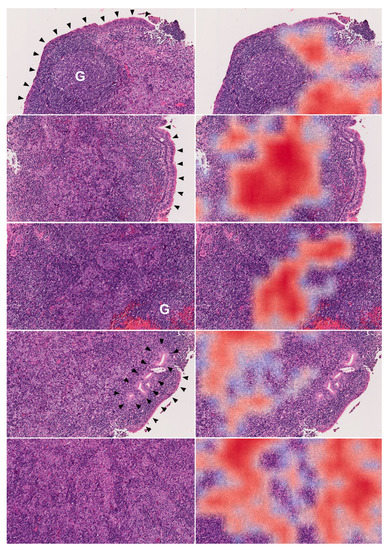

2.2. Key Morphologic Features for Patch-level Identification

4.4. Gradient-weighted Class Activation Mapping